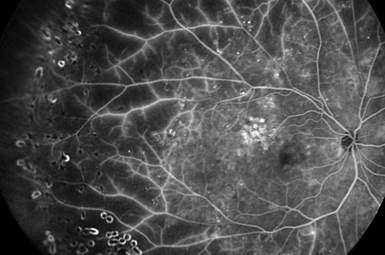

Image courtesy of Heidelberg Engineering, Inc.

Diabetic Retinopathy

Fifty percent of patients with Diabetes for 10 years exhibit some level of eye involvement. Aggressive treatment usually preserves vision.